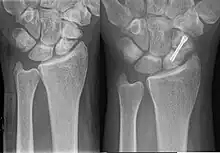

- fixation en chirurgie ambulatoire par technique percutanée,

- vissage en chirurgie classique à ciel ouvert.

Les techniques applicables dépendent du type de fracture et de sa localisation sur l'os. Pour les fractures non déplacées, principalement celles du corps du scaphoïde, la technique percutanée tend à se développer. Elle s'opère sous anesthésie locale, sans hospitalisation du patient, et dure environ 20 à 30 minutes. Ses résultats sont excellents, et la durée d'immobilisation consécutive est réduite à environ deux semaines (contre 8 à 12 semaines sans intervention). Toutefois, un traitement par immobilisation, dans les formes médiales, avec contrôle radiologique et intervention chirurgicale s'il n' y a pas de signe de consolidation, expose à moins de complications qu'une chirurgie immédiate, avec un résultat fonctionnel aussi bon[10].